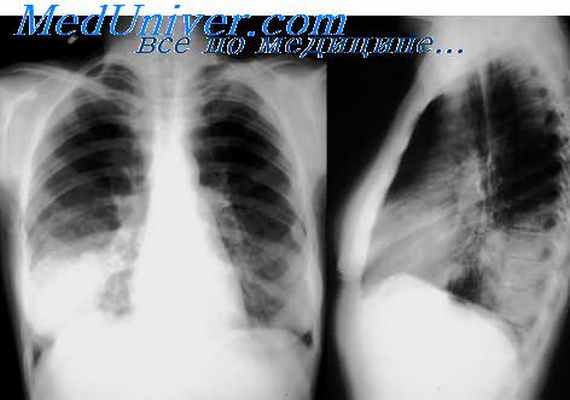

Появляется кашель с выделением зеленоватой гнойной мокроты, кровохарканье. В мокроте обнаруживают нити и споры гриба в виде серовато-зеленоватых хлопьев. При рентгенологическом обследовании выявляются инфильтраты, полости. При аспергиллёзном бронхите наблюдается отёк слизистой, возникают гнойные и лимфоцитарные инфильтраты. При аспергиллёзной пневмонии гифы гриба прорастают ткань лёгкого [12] .

Наиболее частыми признаками заболевания являются - неэффективность антибиотиков широкого спектра, повышение температуры тела более 38°С длительностью более 96 ч, непродуктивный кашель, боли в грудной клетке, кровохарканье и одышка. В 30% случаев повышения температуры может не отмечаться. Иногда клиника аспергиллеза напоминает признаки тромбоза ветвей лёгочной артерии: внезапно возникшие боли в груди и выраженная одышка. Нередко единственным проявлением заболевания служат изменения на рентгенограмме или КТ лёгких.

- рентгенография лёгких и придаточных пазух носа;

- КТ грудной клетки (МСКТ);